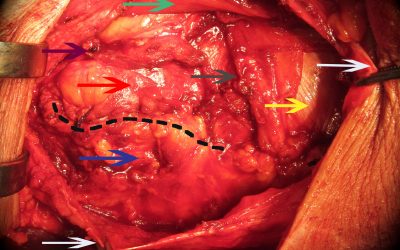

di Enrico Ganz Le immagini presentate in questo articolo evidenziano alcuni momenti di una laparoplastica effettuata per un laparocele in fossa iliaca sinistra (Fig. 2). Il caso si presta per documentare in generale i limiti tecnici di una riparazione in tale area...